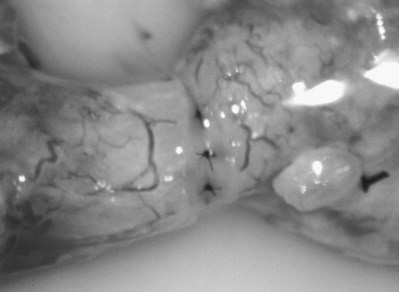

After opening the tunica vaginalis, the epididymis is inspected under the operating microscope. An anastomotic site is selected above the area of suspected obstruction, proximal to any visible sperm granulomas, where dilated epididymal tubules are clearly seen beneath the epididymal tunica (Fig. 22–29). A relatively avascular area is grasped with sharp jeweler’s forceps and the epididymal tunica tented upward. A 3- to 4-mm buttonhole is made in the tunica with microscissors to create a round opening that matches the outer diameter of the previously prepared vas deferens. The epididymal tubules are then gently dissected with a combination of sharp and blunt dissection until dilated loops of tubule are clearly exposed (Fig. 22–30). If the level of obstruction is not clearly delineated after the buttonhole opening is made in the tunic, a 70-µm diameter tapered needle from the 10-0 nylon microsuture is used to puncture the epididymal tubule beginning as distal as possible and fluid is sampled from the puncture site. When sperm are found, the puncture sites are sealed with microbipolar forceps, a new buttonhole is made in the epididymal tunic just proximally, and the tubule is prepared as described previously.

Figure 22–29 An anastomotic site is selected above the area of suspected obstruction, proximal to any visible sperm granulomas, where dilated epididymal tubules are clearly seen beneath the epididymal tunica, as marked by an arrow.

Figure 22–30 The epididymal tubules are then gently dissected with a combination of sharp and blunt dissection until dilated loops of tubule are clearly exposed.